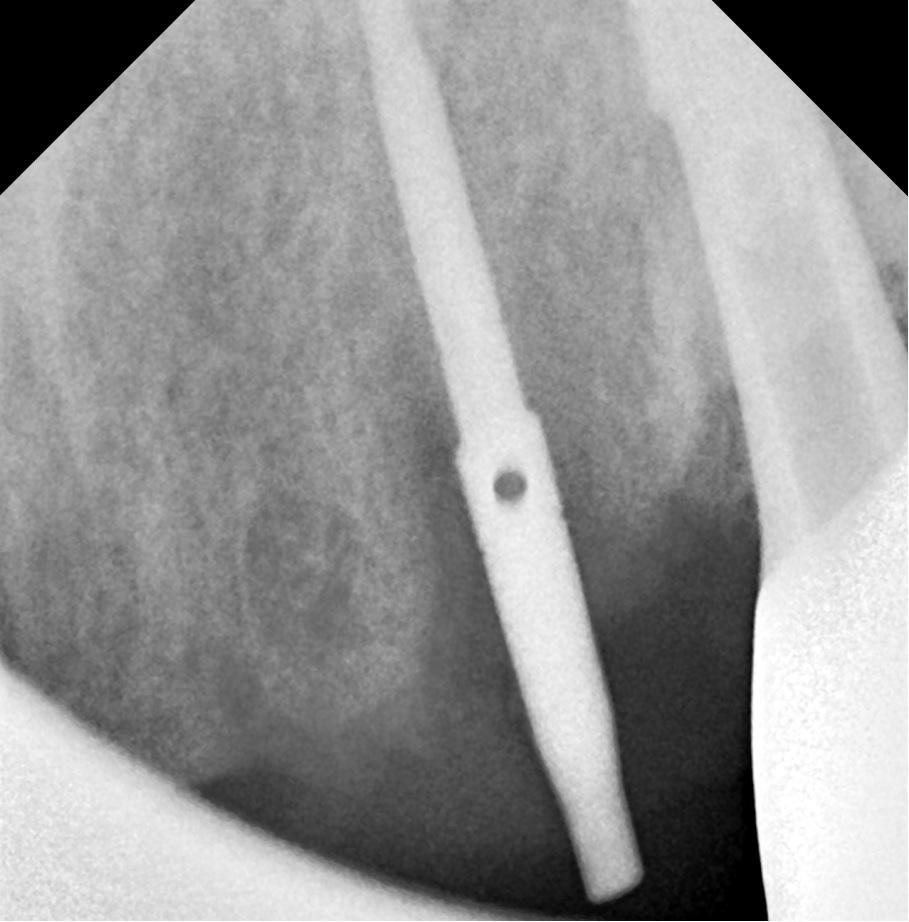

엑스레이 사진상에 위 앞니쪽 모든 치아뿌리 끝에 염증 병소가 보이고, 특히 우측 견치(송곳니)는 심한 우식으로 치관부(머리부분)가 전혀 남아있지 않은 상태였습니다.

해당 치아 3개 모두 발거하고 임플란트 수술 중간중간 방향을 확인하며 수술을 마무리 하였습니다.

치아 뿌리 끝 염증부위에는 모두 골이식을 동반하였으며, 수술 직후 바로 본을 떠서 다음날 아침 일찍 임시치아를 끼워드리기로 계획하였습니다.

임플란트는

덴티움社의 Superline 을 사용했으며 해당 부위 모두 적당한 위치로 식립되었습니다.

모든 임플란트에 연결하여 바로 임시치아를 만들어드리려고 하였으나 우측 송곳니 (사진상 좌측) 에는 치조골 상태가 좋지 않아서 다량의 골이식 및 임플란트를 잇몸 안에 묻어두기로 결정하였습니다.

따라서 가운데 임플란트와 좌측 송곳니 임플란트 (사진상 우측)만 기둥을 연결하여 임플란트 본을 떴습니다.